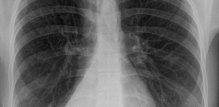

Atelektaza pluća